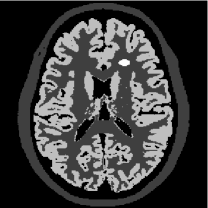

For the numerical studies we set up an artificial brain phantom (see Figure 5) with a size of x pixels using data from BrainWeb [15], which features the typical challenges of a joint reconstruction.

![]() |

\begin{overpic}[height=108.405pt]{figure5a_cbar} \put(0.75,91.0){\small$10$} \put(2.75,3.0){\color[rgb]{1,1,1}{$0$}} \end{overpic} | ![]() |

\begin{overpic}[height=108.405pt]{figure5a_cbar} \put(2.75,91.0){\small$1$} \put(2.75,3.0){\color[rgb]{1,1,1}{$0$}} \end{overpic} | ![]() |

| (a) PET phantom | (b) MRI phantom | (c) PET data |

First of all, both phantoms feature the exact same location of edges everywhere except for the two artificially added lesions in the upper right part of the PET image and the left part of the MR image. Both have been added to illustrate a common joint reconstruction problem, namely the introduction of artifacts, i.e. features not present in one of the images that are transferred artificially to the other. While the locations of the edges are equal, the jumps across the edges are not, meaning that we e.g. have a “step up” from gray matter to white matter in the MR image, while we have a “step down” in the PET image. Furthermore, we point out the different range of image intensities. This imposes the issue of locally different gradient heights, which cannot be dealt with thoroughly by a global scaling of the data. Summing up we find the following features:

-

•

Equal edge locations (except for two lesions),

Equal and different edge orientations,

Different height of jumps across edges,

Different scale.